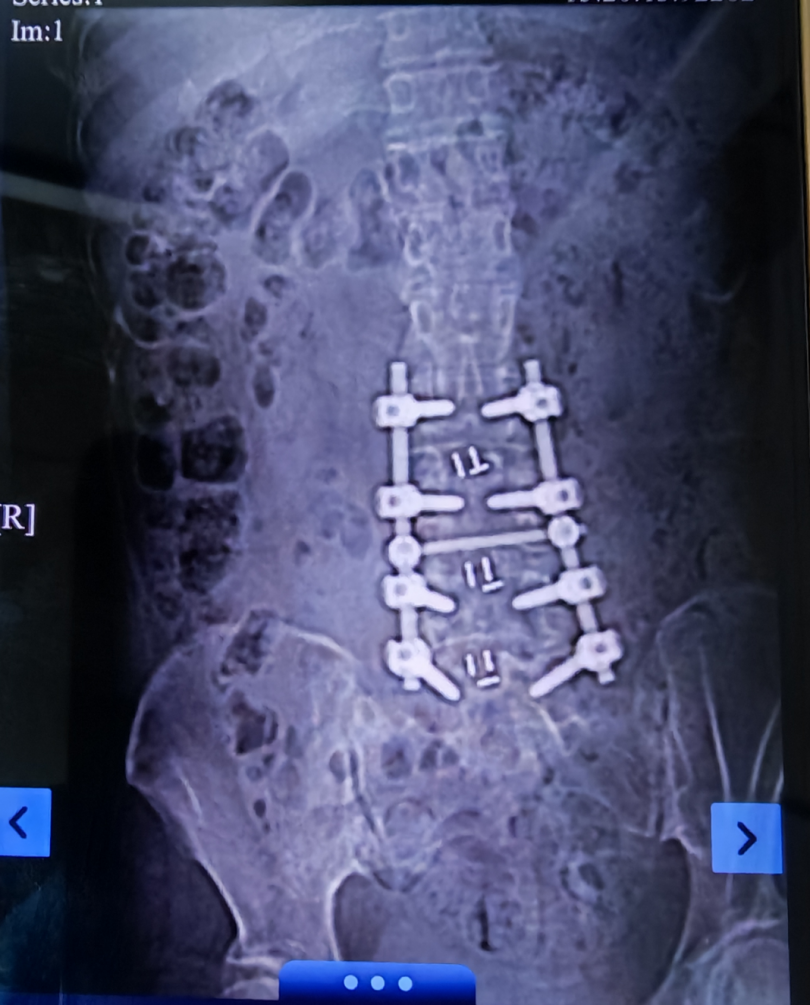

据悉,该患者确诊白血病后,腰椎穿刺是其诊疗过程中的关键环节。腰穿成功,既能获取脑脊液标本完成病情精准评估,又能直接注射化疗药物,有效预防中枢神经系统白血病。然而,该患者几年前因腰椎疾病接受过腰椎内固定手术,椎体内金属固定物的存在、局部解剖结构的改变以及术后瘢痕组织的增生,给此次腰椎穿刺带来了多重挑战。常规腰穿操作使用传统解剖定位的方式识别穿刺间隙,穿刺难度极大,还可能在操作中损伤神经与血管,引发不良风险。更关键的是,若腰穿操作未能成功实施,将直接影响患者白血病病情的准确评估和化疗药物的鞘内注射,对整体治疗进程造成显著影响。

面对这一棘手情况,血液内科主任李昕、成倩主治医师发起了MDT进行讨论。麻醉科廖琴主任结合科室技术优势,指定超声引导下穿刺经验丰富的卿文祥主治医师进行此次腰穿。超声技术可实时清晰呈现腰椎间隙、硬膜、神经根及周围软组织解剖结构,精准避开金属固定物与重要神经血管,锁定最佳穿刺路径,大幅降低操作风险与难度。卿文祥医生完成超声定位后,穿刺仅耗时约1分钟,创伤小,患者全程生命体征平稳,无明显不适。术后脑脊液检查结果为临床制定治疗方案提供了重要依据,化疗药物的成功注射也为控制病情、改善预后创造了有利条件。